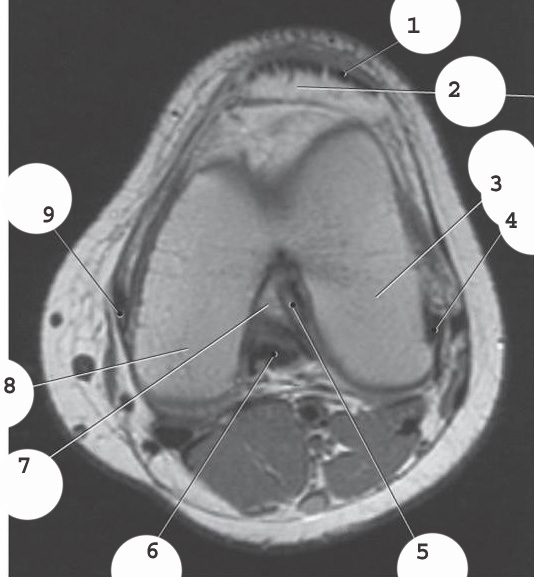

quadricep tendon

lateral colateral ligament